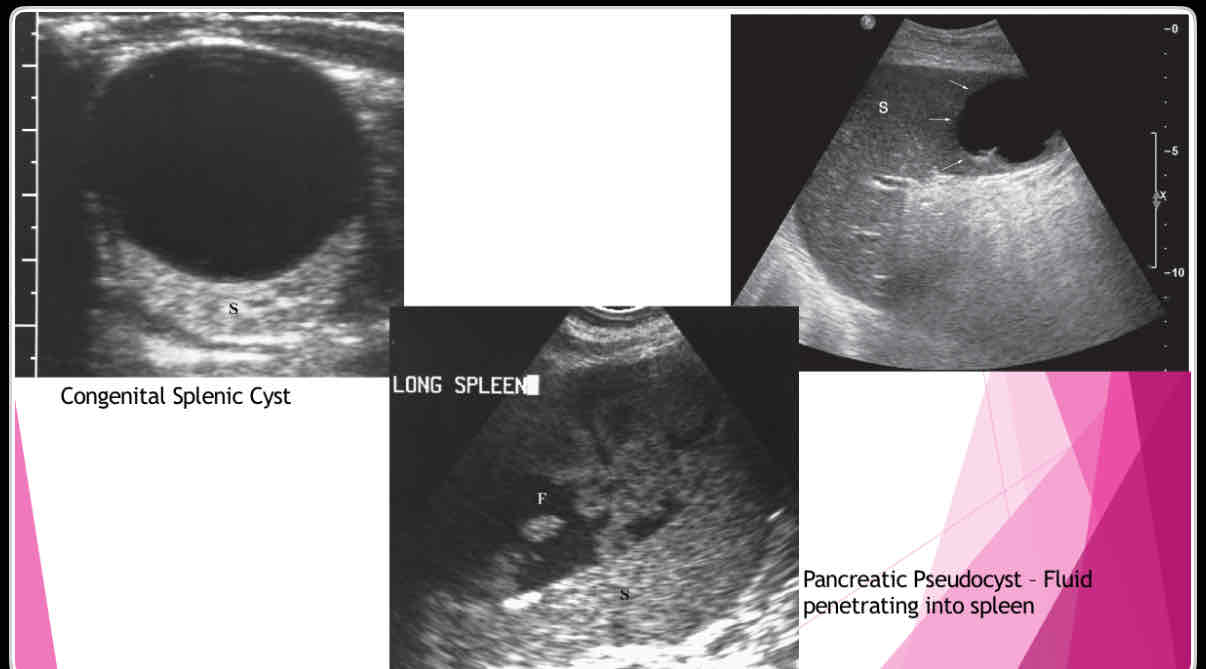

What does the following describe?

•Anechoic, well-defined walls, enhanced sound transmission

•Sharply demarcated wall, multilocular internal structure representing daughter cyst, mural calcifications

•Large cysts, dense, clearly defined walls May not have well-defined wall, mural calcifications Single or multiple simple cysts

splenic cysts

What are the different types of splenic cysts?

•Can be Congenital

•Can also be Acquired

• Echinococcal (hydatid)

•Epidermoid or epithelial

•Posttraumatic or postinflammatory pseudocysts

What does the following describe?

•True cysts lined by squamous epithelium

•Typically solitary, 10 cm

•Wall may be calcified and internal contents echogenic

Epidermoid or epithelial

What does the following describe?

•Polycystic kidney disease lymphangioma,

•extension of pancreatic pseudocyst

-Erode into spleen due to proximity

-May weaken vessels causing pseudoaneurysms and bleeding into pseudocyst

Posttraumatic or postinflammatory pseudocysts